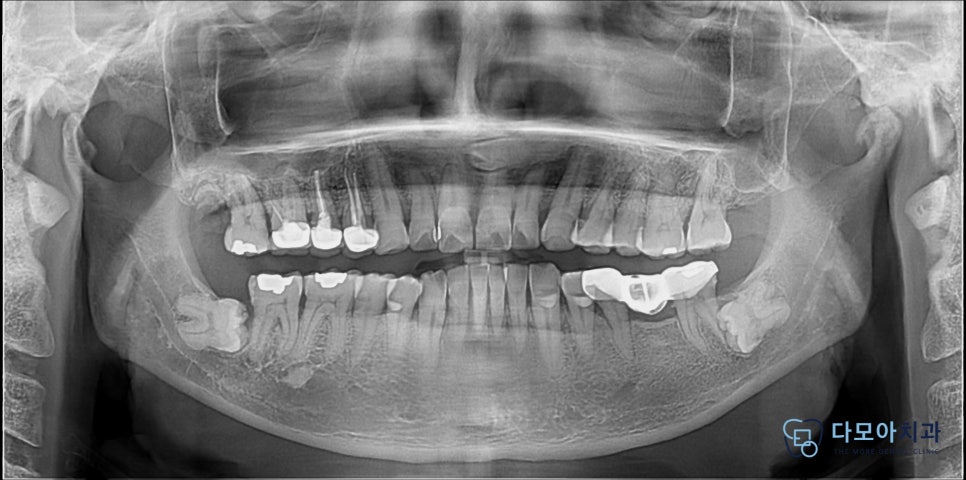

실제로 58세로 양쪽에 수평으로 누워있는

완전 매복 사랑니가 있으신 환자분께서

저희 치과를 방문해주셨는데요.

엑스레이를 확인해 보니,

양쪽 모두 사랑니가 수평으로 기울어져 있었으며

완전 매복 사랑니였습니다.

환자분께서는 우측 사랑니가

통증이 있다고 하셨는데요.

(엑스레이 상에서는 왼쪽입니다.)

엑스레이 상에서 하치조신경관 맞닿아 있는것 같아 보여서

3D CT 촬영을 통해,

3차원적으로 위치관계를 분석하였습니다.